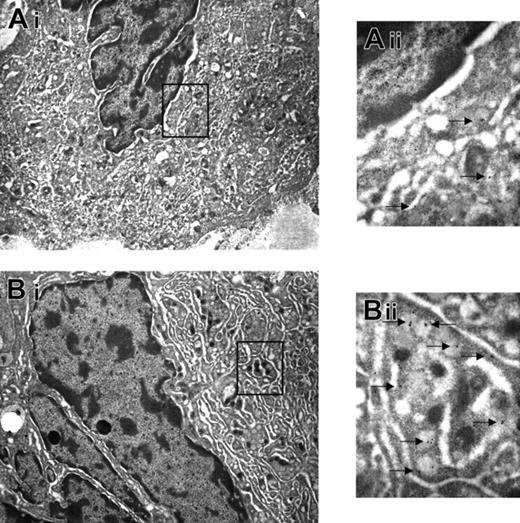

TPO treatment had profound effects on the morphology of Mks both in wild-type and GATA-1low mice. In wild-type mice, the overall morphology of the Mks in the spleen became less mature, as revealed by reduced localization of P-selectin (Schmitt et al32 and results not shown) and von Willebrand factor (Table 2) on the α-granules. In addition, a significant portion (31 ± 2.6%) of these Mks had the heavy-electron dense para-apoptotic morphology originally described for GATA-1low Mks22 and contained neutrophils embedded in the cytoplasm, as confirmed by myeloperoxidase immunostaining (Figure 4). In contrast, in TPO-treated GATA-1low mice, the morphology of the Mks became more mature with clearly delineated platelet territories and significant increase, both in number and in localization to the α-granules, of von Willebrand factor–related gold particles (Figure 5; Table 2). These stage III Mks, never detected in untreated mutants,22 represented 28.5% of the Mks in spleen from TPO-treated GATA-1low Mks.

TPO treatment restored Mk maturation in GATA-1low mice. Immunoelectron microscopy for von Willebrand factor of Mks from the spleen of untreated GATA-1low mouse (A) and from a mutant mouse after 7 days of TPO treatment (B). The cytoplasm of the Mks from TPO-treated animals contains clearly recognizable platelet territories with numerous electron-dense granules, which, when analyzed at higher magnification, contain several von Willebrand factor–related gold particles (Bii). The rectangle in panels A and B indicates the region of the Mks shown at higher magnification in Aii and Bii, respectively. The arrows in Aii and Bii indicate von Willebrand factor–related gold particles. Magnification, × 4400 (Ai,Bi) and × 30 000 (Aii,Bii). Numerical aperture of the objective lenses: 0.1.